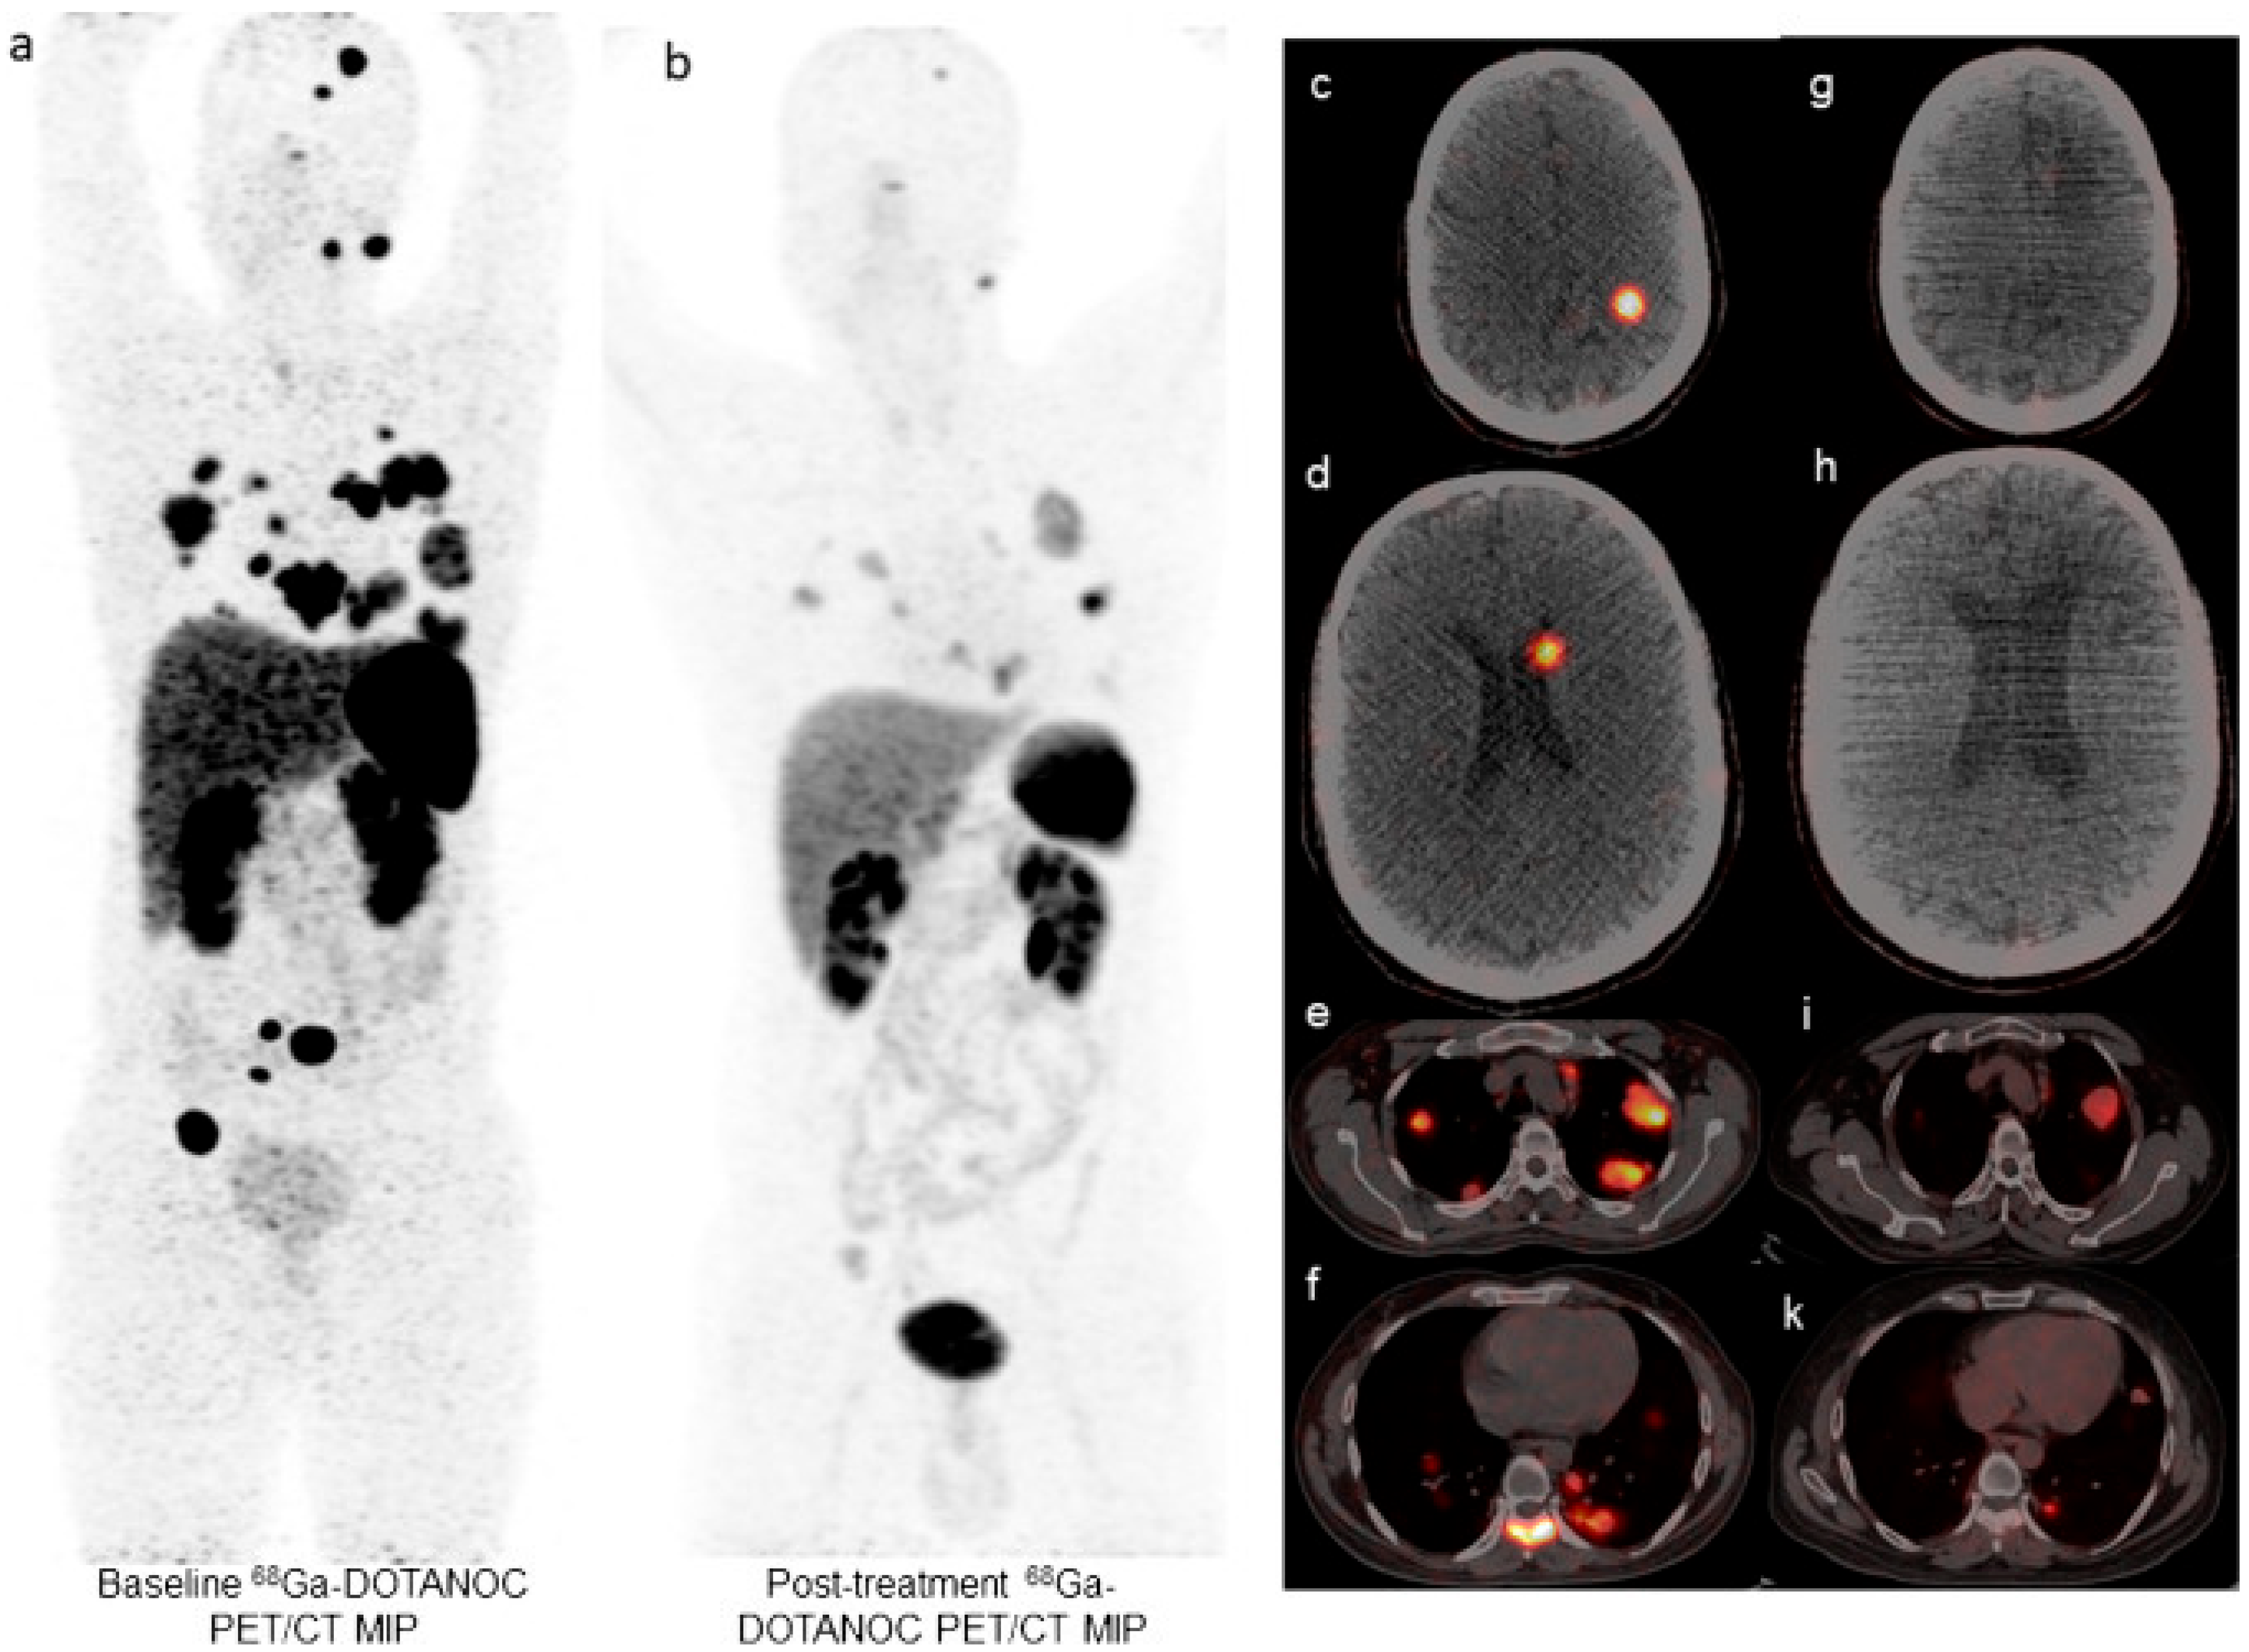

- Kratochwil, C.; Giesel, F.L.; Bruchertseifer, F.; Mier, W.; Apostolidis, C.; Boll, R.; Murphy, K.; Haberkorn, U.; Morgenstern, A. 213Bi-DOTATOC receptor-targeted alpha-radionuclide therapy induces remission in neuroendocrine tumours refractory to beta radiation: A first-in-human experience. Eur. J. Nucl. Med. Mol. Imaging 2014, 41, 2106–2119. [Google Scholar] [CrossRef] [PubMed]

- Yang, H.; Zhang, Y.; Li, H.; Zhang, Y.; Feng, Y.; Yang, X.; Chen, Y. Efficacy and Safety of 225Ac-DOTATATE in the Treatment of Neuroendocrine Neoplasms with High SSTR Expression. Clin. Nucl. Med. 2024, 49, 505–512. [Google Scholar] [CrossRef]

- Yadav, M.P.; Ballal, S.; Sahoo, R.K.; Bal, C. Efficacy and safety of 225Ac-DOTATATE targeted alpha therapy in metastatic paragangliomas: A pilot study. Eur. J. Nucl. Med. Mol. Imaging 2022, 49, 1595–1606. [Google Scholar] [CrossRef]